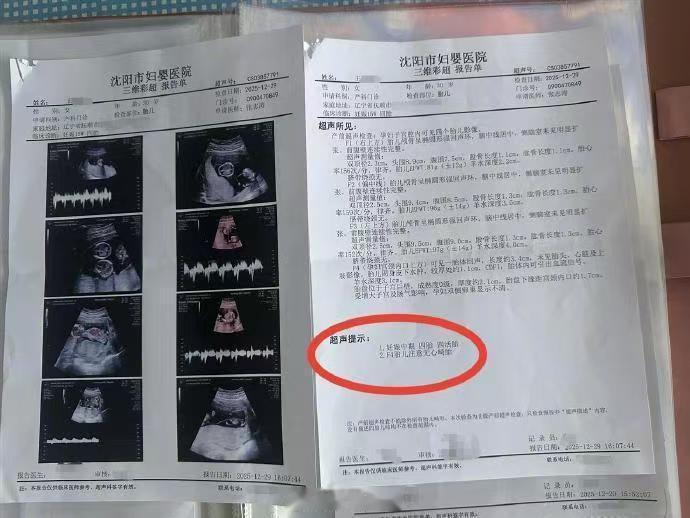

辽宁抚顺的一位准妈妈最近经历了人生中过山车般的时刻。怀孕16周的王女士,原本只是按部就班地进行产检,却在医院拿到了一份极其罕见的诊断报告。从去年11月到12月,短短一个月的时间里,她在医院进行了四次产检,每一次彩超单上的图像都在发生变化——最终确认,她怀上了四胞胎。 这并非普通的四胞胎。根据相关医生的诊断,王女士怀上的是同卵四胞胎。在医学领域,同卵四胞胎的发生率极低,属于非常罕见的个案。更复杂的情况在于,医生指出第四个胎儿为“无心畸胎”。这是一个专业性很强的术语,意味着这个胎儿虽然没有正常的心脏发育,但依然依赖其他胎儿的血液循环在母体内生存。这种特殊的医学状况,无疑给整个孕期增添了巨大的不确定性和风险。 对于普通家庭而言,多胞胎往往意味着双倍的喜悦,但在医学视角下,这更多代表着高风险妊娠。从数据来看,自然受孕情况下同卵四胞胎本就凤毛麟角,而伴随无心畸胎的情况更是让保胎之路布满荆棘。王女士在抚顺当地医院进行的这四次检查,实际上是一个不断排查和确认的过程。每一次彩超,不仅是在数胎儿的数量,更是在评估母体和每一个胎儿的生存质量。 网友们对此议论纷纷,有人感叹生命的奇妙与不易,也有人为即将到来的抚养压力感到担忧。毕竟,四个孩子的降生,对家庭的经济状况、父母的精力都是极大的考验。目前摆在王女士和家人面前的,不仅是喜悦,还有如何根据医生的专业建议,制定最科学、最安全的后续妊娠方案。 这起事件也给广大备孕及孕期女性提了个醒:规范的产检流程至关重要。像王女士这样,通过连续、定期的超声检查,才能及时发现多胎妊娠及胎儿发育异常等特殊情况。面对罕见病例,医学干预和监测是保障母婴安全的最有效手段。祝愿这位准妈妈能平安度过接下来的孕期,也希望这个小生命群体能在现代医学的保驾护航下,迎来最好的结局。 以上内容仅供参考和借鉴